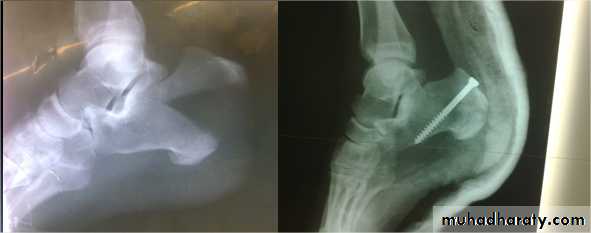

Calcaneal fractures

Usually after FFH.Associated injuries: spine, pelvis, hip or base of skull.

Extra-articular fractures: need closed treatment. Have good prognosis.

Intra-articular fractures:

involve superior articular surface. May be comminuted.

Treatment

Admit to hospital, elevate the leg and apply ice-packs until swelling subside.

Undisplaced fractures: closed treatment.

Displaced fractures: ORIF with screws.

Calcaneal tuberosity fracture

Complications

Broadening of the heel

Talocalcaneal stiffness and OA